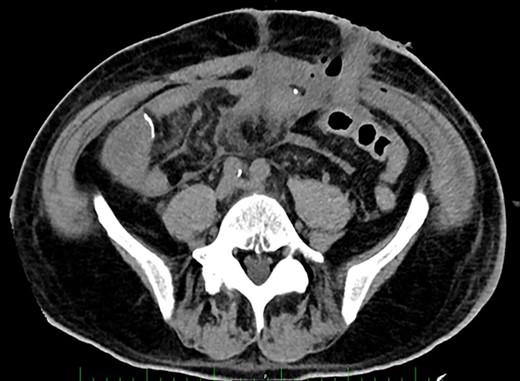

Post-operative Day 14. Abdominal CT-scan with free intraperitoneal fluid, without sign of ileus, perforation or anastomosis release.

Renal replacement therapy was required until Day 10, mechanical ventilation and catecholamines support until Day 12. On Days 13 and 14, the patient did not present any fever or abdominal pain, CRP levels were at 125 mg/l and 196 mg/l, respectively and white blood cell (WBC) counts were stable at 20 G/L. Blood levels of PSP were determined to be 387 ng/ml on Day 14, measured on the point-of-care abioSCOPE® device (Abionic SA, Epalinges, Vaud, Switzerland). This high concentration of PSP (>290 ng/ml [4]) triggered an abdominal CT-scan which showed free fluid, no sign of ileus, perforation or anastomosis release (Fig. 2). Despite this result and absence of clinical signs, the patient was rescheduled for surgery based on the high PSP value. The laparotomy revealed a loosening of the ileal anastomosis and confirmed the presence of a diffuse post-operative peritonitis. A second distal ileostomy was performed along with abundant peritoneal lavage, abdominal wall VAC. Escherichia coli, Enterococcus faecalis and S. aureus were detected in the peritoneal fluid cultures 48 h later, and antibiotic therapy with imipenem/cilastine/fluconazole was maintained. From Day 14 onwards, PSP, CRP and WBC were dosed daily. These three biomarkers progressively decreased to reach values of 225 ng/ml, 157 mg/l and 12.3 G/L, respectively on Day 18.